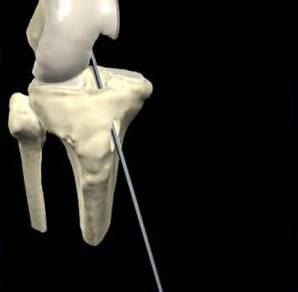

1.準(zhǔn)確定位,建立骨隧道。

脛骨點(diǎn)選取

股骨點(diǎn)